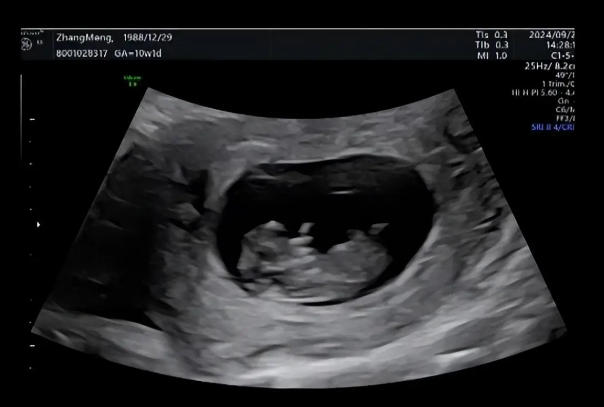

在孕早期出现先兆流产征兆时,B超检查是评估胚胎存活状态的关键手段。通过经阴道或腹部超声波,医生可清晰观测孕囊位置、卵黄囊发育及原始心管搏动情况。对于有复发性流产史或辅助生殖受孕的孕妇,临床指南建议通过系列B超动态监测胚胎发育速度,这与单次检查相比能更早发现胚胎停育风险。

以典型病例为例,32岁经产妇张女士因抗心磷脂抗体阳性,孕早期即出现子宫动脉血流阻力增高。在免疫调节治疗期间,医生为其制定了每3日一次的超声监测方案,通过连续18次检查及时调整肝素用量,最终子宫动脉PI值从2.8降至1.2,成功维持妊娠至足月。